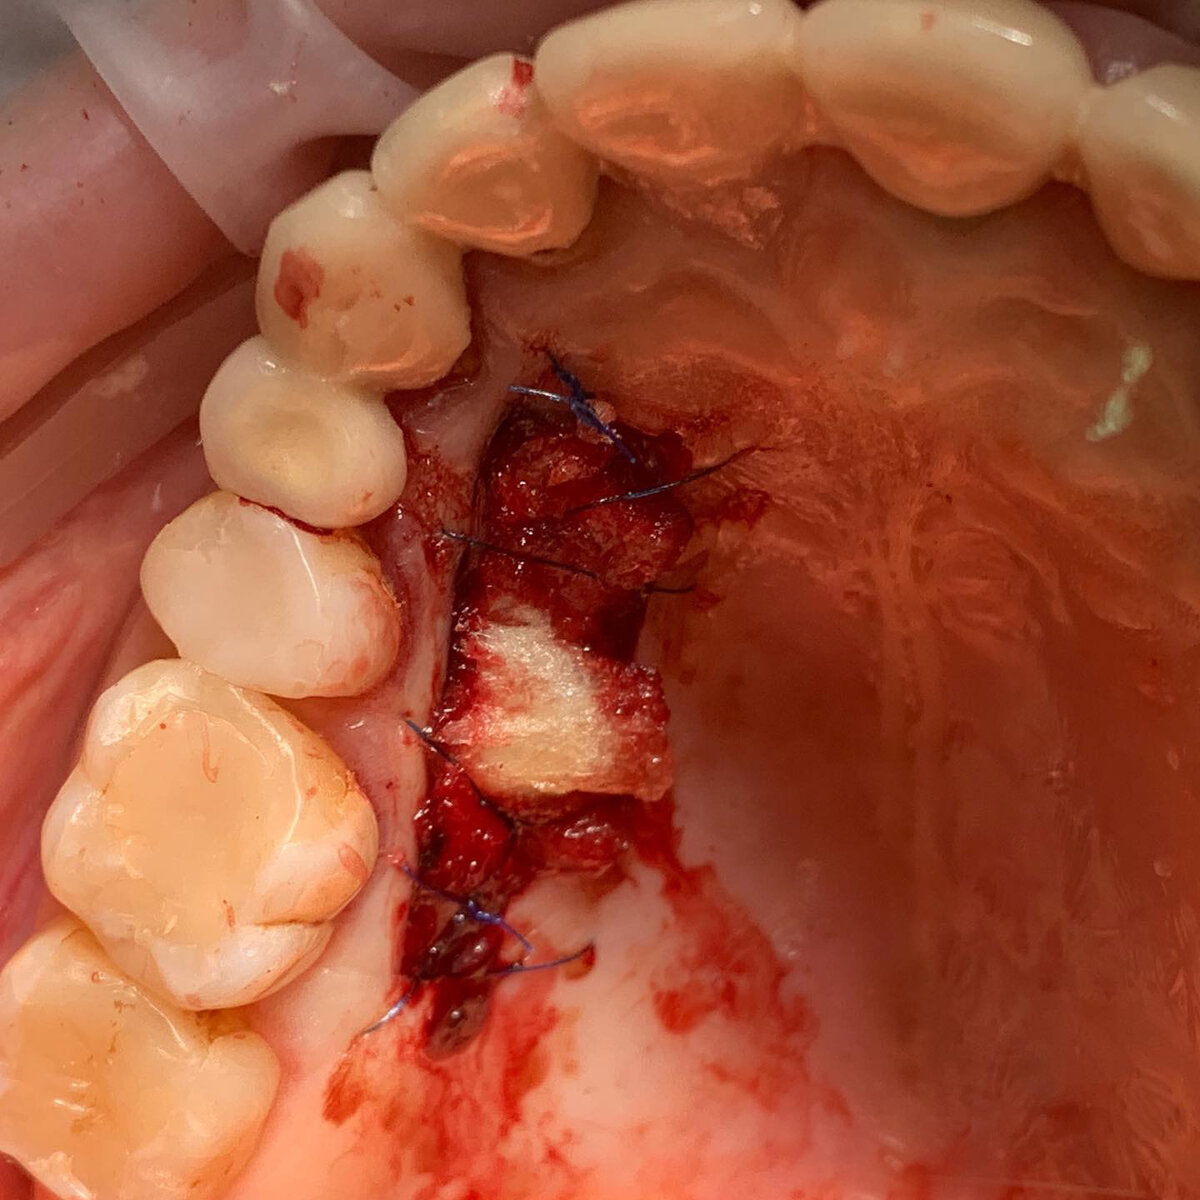

Для восстановления зубов 36 и 37 провели:

📌расщепление костной ткани + горизонтальная аугментация (подсадка кости по ширине) с одномоментной установкой двух имплантантов.

📌из-за недостатка прикрепленной слизистой пересадил свободный десенной трансплантат с нёба

📌после приживления десны провели установку формирователей и протезирование циркониевыми коронками

⚡️Идея работы в том, чтобы не просто провести установку имплантантов с одновременным расщеплением кости.

⚡️А задача выполнить восстановление кости, зубов так, чтобы это было на длительный срок, на всю жизнь.

⚡️Для этого нужно, чтобы ширина кости была восстановлена до идеальной. Но не менее важно создать вокруг имплантантов прикрепленную неподвижную десну, чтобы налёт и микробы не попадали под десну и не приводили к воспалению и периимплантиту.